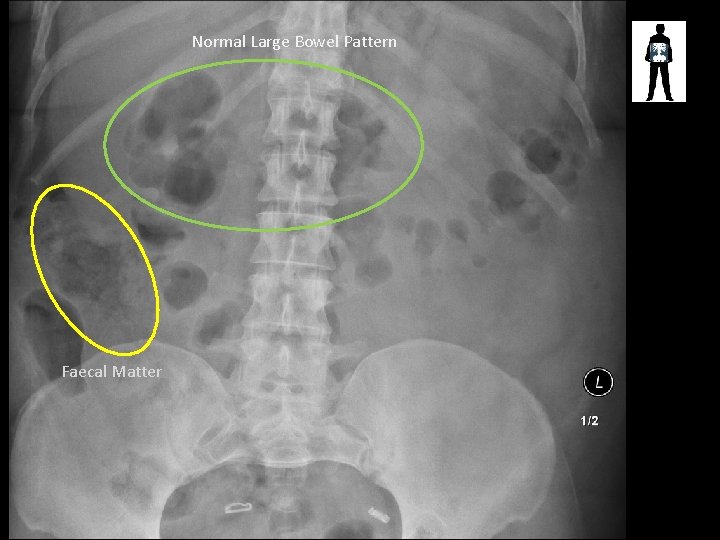

Normal Large Bowel Pattern Faecal Matter